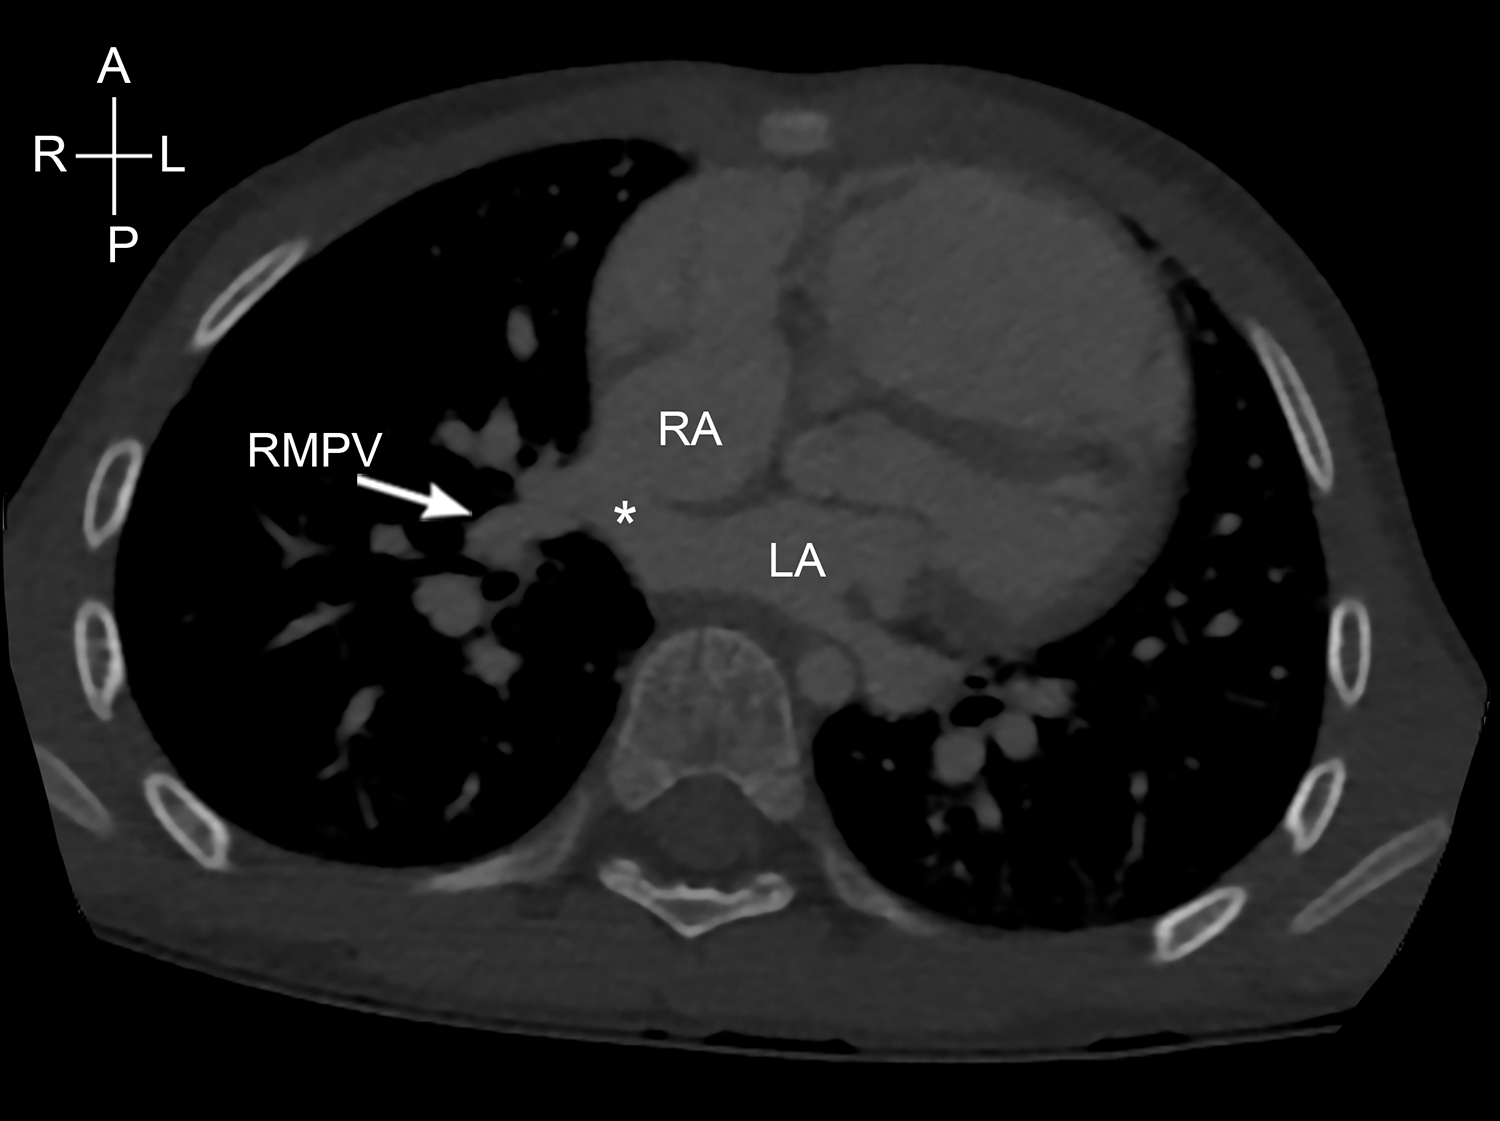

The most common type of partial anomalous pulmonary venous drainage noted in this cohort was right upper and/or right middle pulmonary veins draining into the right superior caval vein. The patterns of insertion of the pulmonary veins are variable with low right superior caval vein being the commonest insertion point (19 of 37 patients). In ten cases, the anomalous pulmonary veins inserted into the right superior caval vein and right atrial junction (Fig 3). In three cases, the anomalous pulmonary veins drain directly into right atrium.

Figure 3. Computed tomography demonstrating right middle pulmonary vein (RMPV) draining to the right superior caval vein/right atrium junction. LA=left atrium; RA=right atrium.